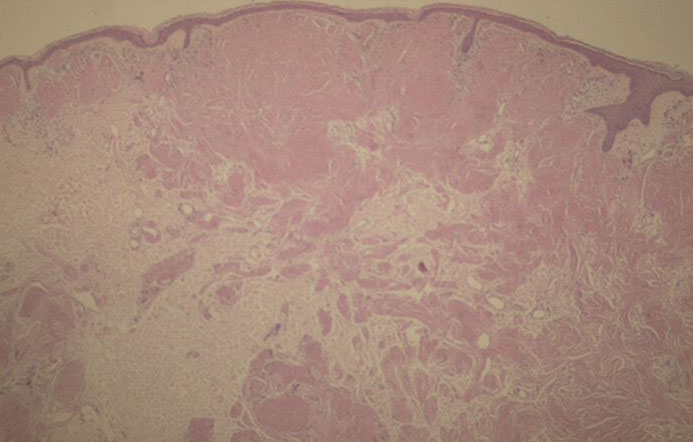

Nodular amyloid =الداء النشواني العقيدي